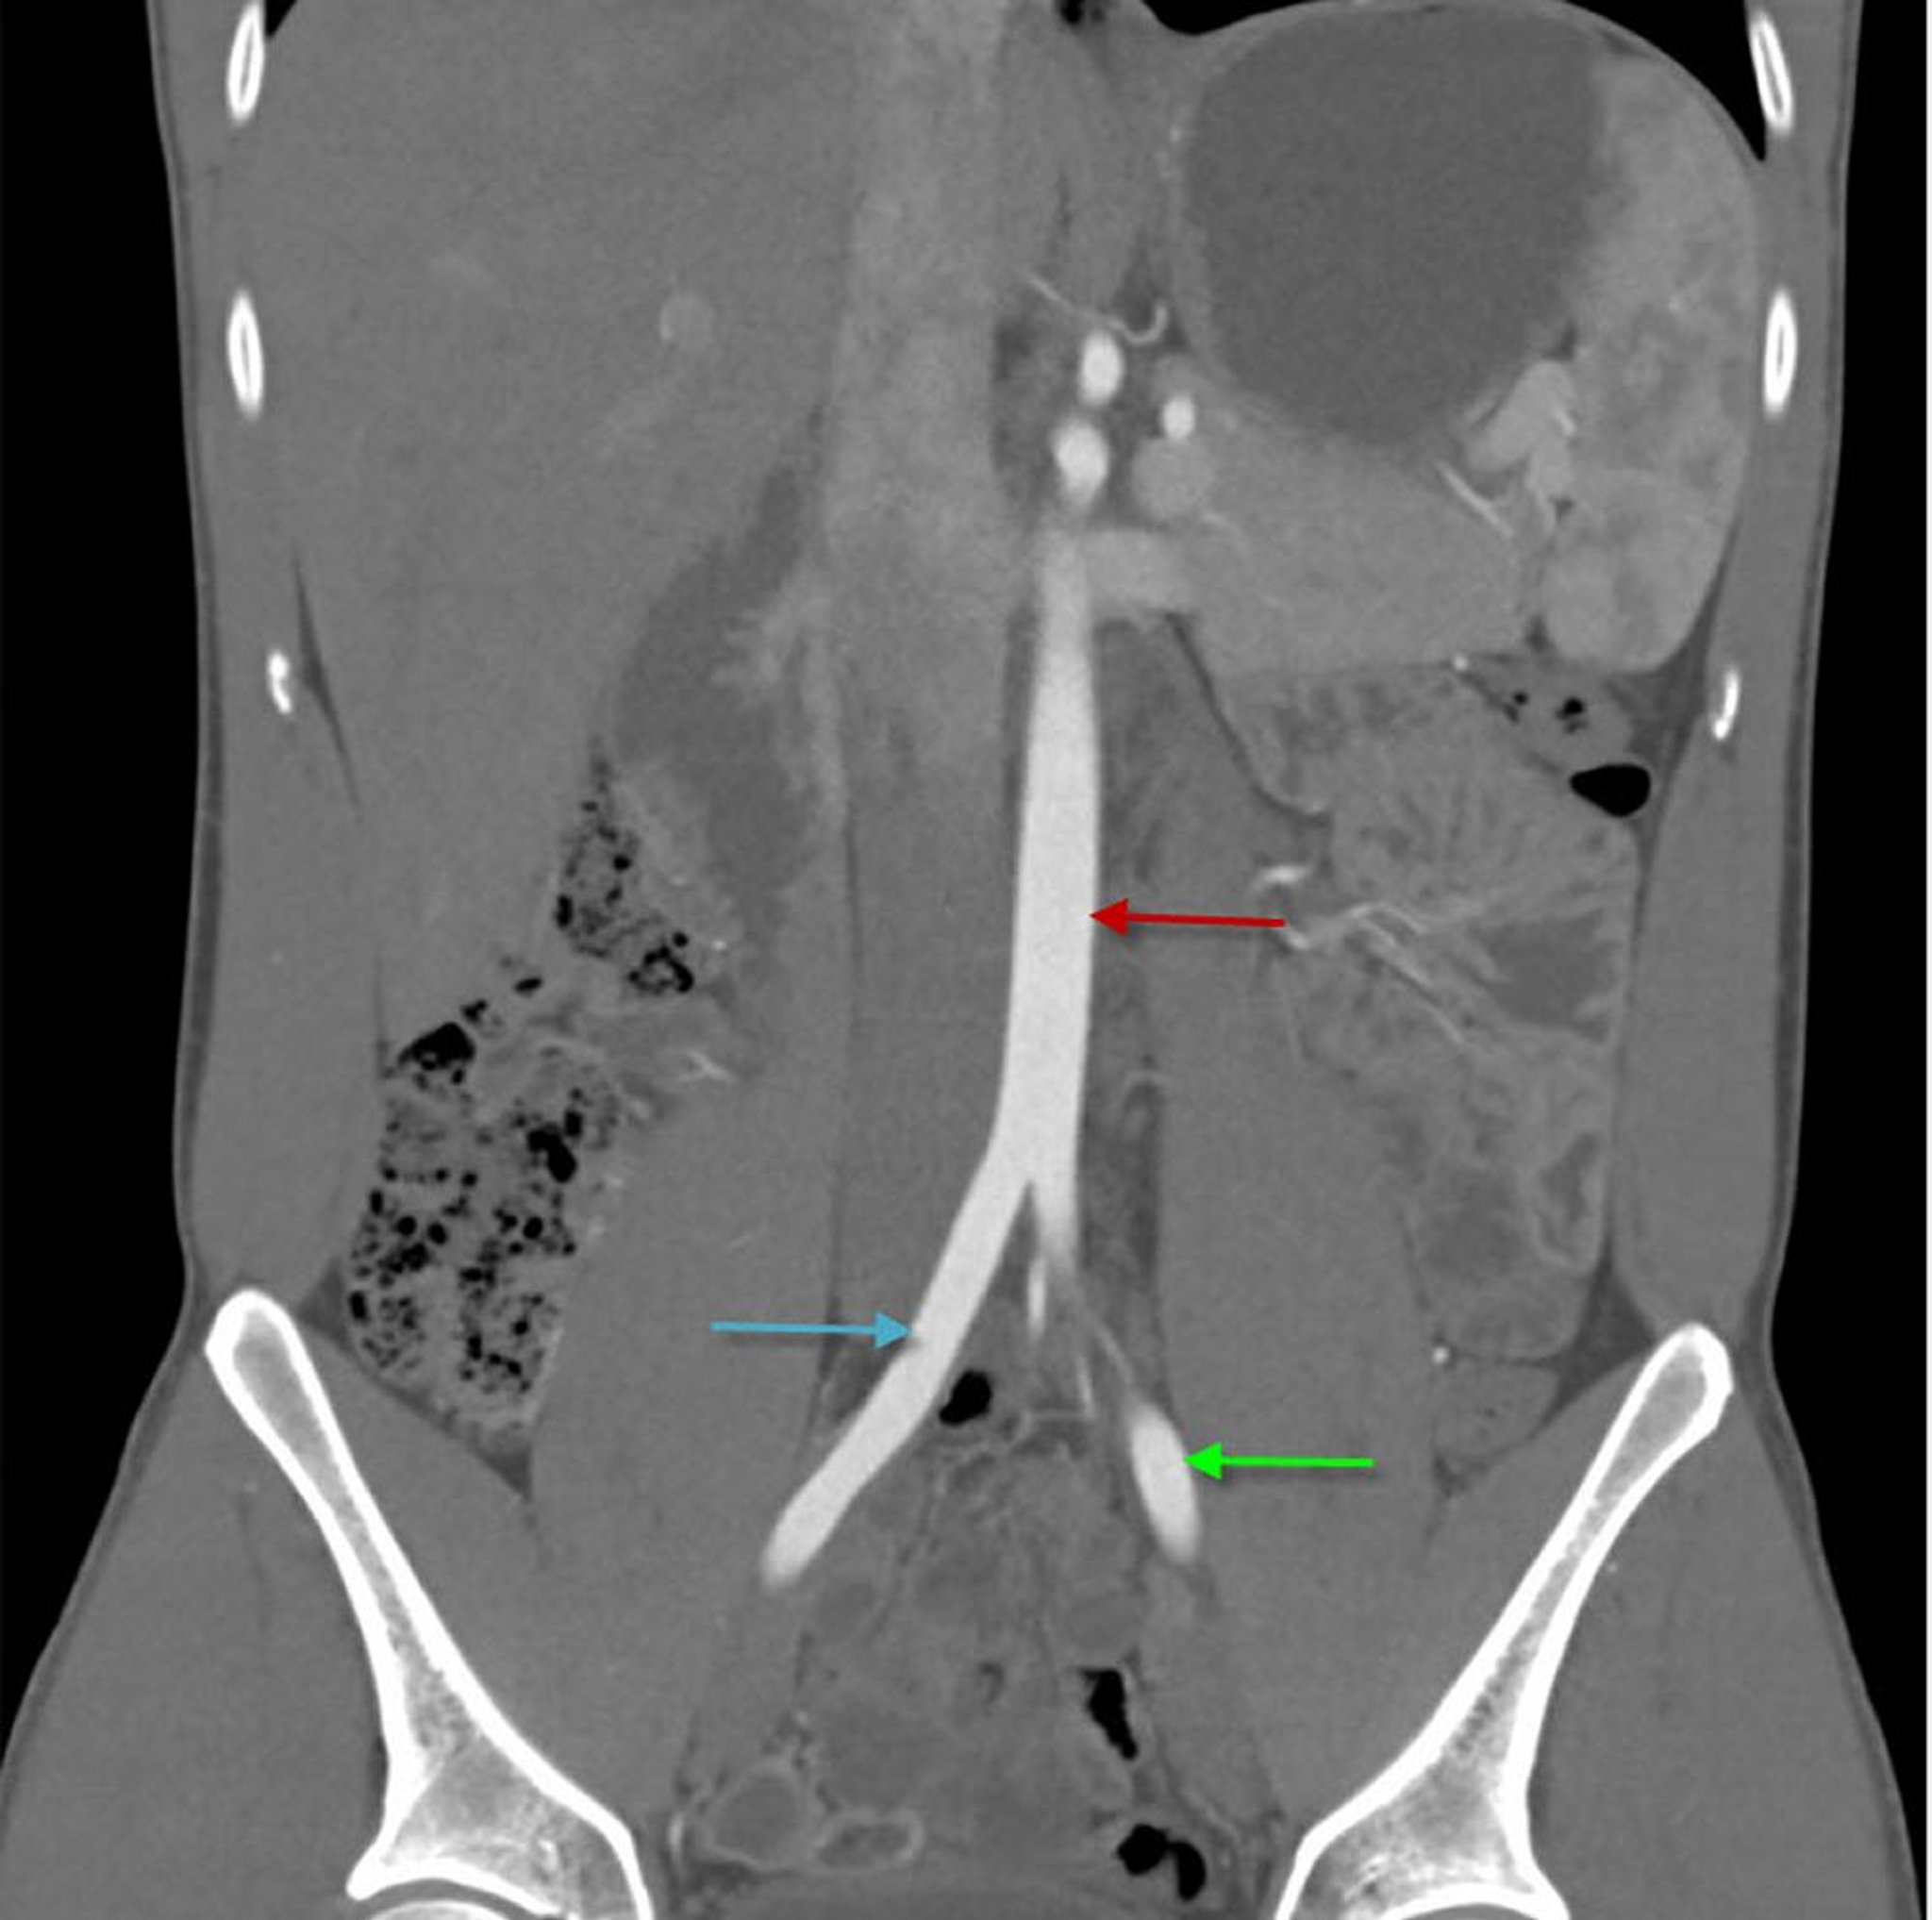

КT-ангиография брюшной полости, показывающая брюшную аорту (фронтальная проекция)

На данном изображении показана абдоминальная аорта (красная стрелка), разделяющаяся на правую (синяя стрелка) и левую (зеленая стрелка) общую подвздошную артерию.